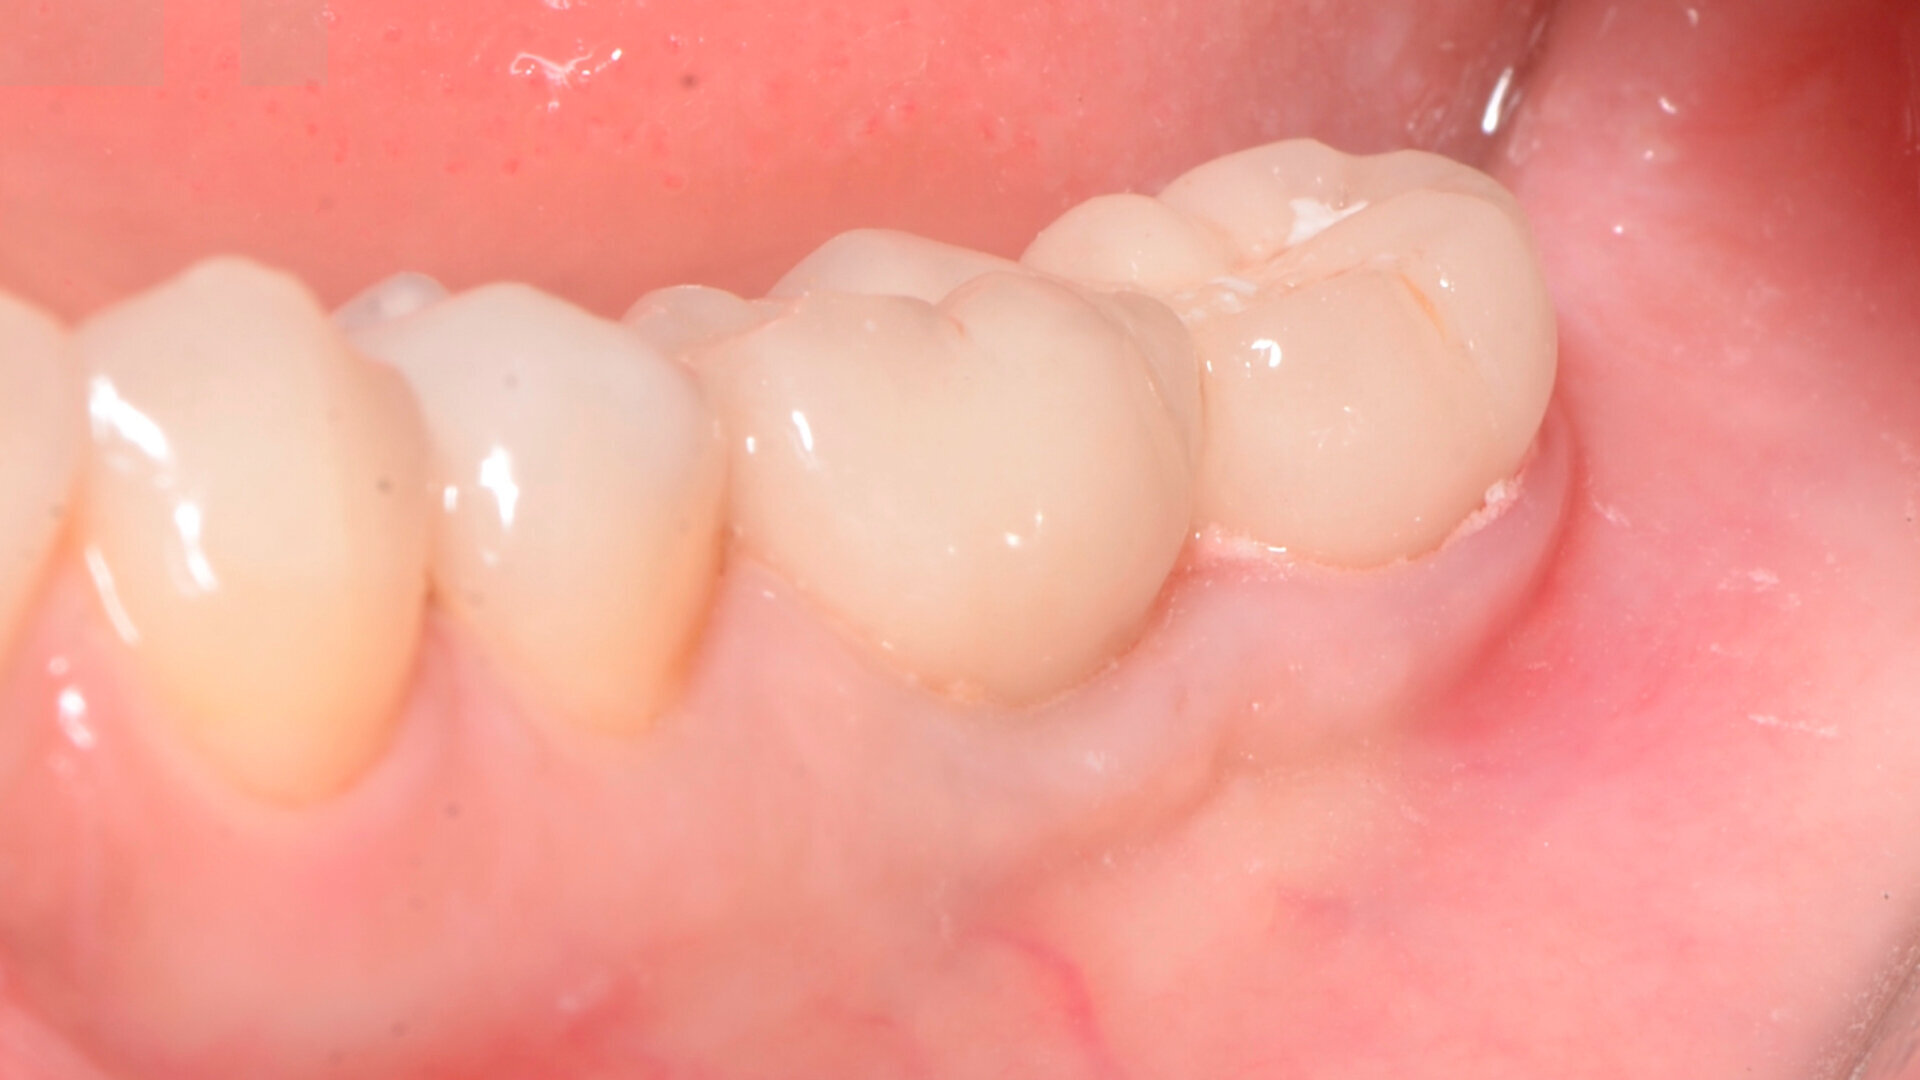

Aspect clinique de la zone des tissus mous péri-implantaires lors du suivi à cinq ans. (Photo : Dr Cosimir Dima)

La profondeur de sondage du site péri-implantaire a été mesurée au niveau du point médian inter-proximal, et la valeur la plus élevée entre le bord des tissus mous et le fond du sulcus péri-implantaire a été retenue. Une lime endodontique ISO n° 15 a été utilisée pour évaluer l’épaisseur de la muqueuse péri-implantaire vestibulaire à 2 mm des bords des tissus mous en mésial, distal et médial de la plate-forme de l’implant (point de référence). La muqueuse kératinisée a été évaluée au début du traitement, puis lors des suivis au moyen d’une sonde parodontale. Les mesures ont été prises verticalement au niveau du point médio-vestibulaire, depuis la plate-forme de l’implant jusqu’au bord libre de la gencive. Elles ont été effectuées en préopératoire, immédiatement après l’intervention, puis à quatre semaines, un an et deux ans par la suite. Les paramètres cliniques (largeur de la muqueuse kératinisée, volume de la muqueuse, et recouvrement de la récession gingivale) ont été enregistrés au début du traitement, et lors de chaque visite de suivi. La largeur initiale de la muqueuse kératinisée était minimale (1 mm). À quatre semaines, le gain de largeur de la muqueuse kératinisée était de 2 mm, puis de 3 mm après un an, et de 4 mm après cinq ans.

À quatre semaines, le gain de volume de la muqueuse était de 3 mm, puis de 4 mm après un an, et de 5 mm après cinq ans. Le recouvrement de la récession était déjà complet après quatre semaines, et l’était toujours après un an et après cinq ans.

Le patient présentait une mobilité des tissus mous péri-implantaires, une largeur de tissu kératinisé inférieure à 1 mm, et une épaisseur de la muqueuse inférieure à 2 mm. Le bord des tissus mous se situait au niveau de la plate-forme de l’implant. L’utilisation de cette technique a permis une amélioration significative de la qualité des tissus mous péri-implantaires, et l’obtention d’un gain de tissu kératinisé attaché de 4 mm. Le lambeau de rotation utilisé dans la technique Snake offre les avantages d’une greffe de muqueuse kératinisée libre, et permet ainsi d’augmenter la largeur de la muqueuse vestibulaire péri- implantaire. Il assure également un apport sanguin très satisfaisant et la stabilité du lambeau pédiculé, ce qui se traduit par une rétraction moindre au fil du temps, par rapport à une greffe de tissu mou libre.